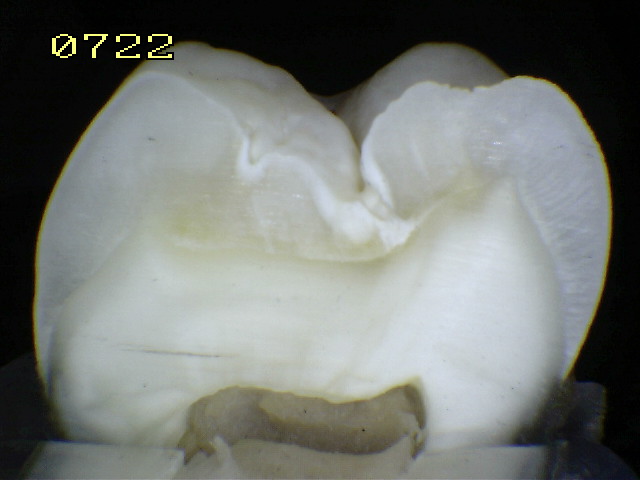

Espécimen Nº 32 |

Corte sagital |

Código 2 histológico